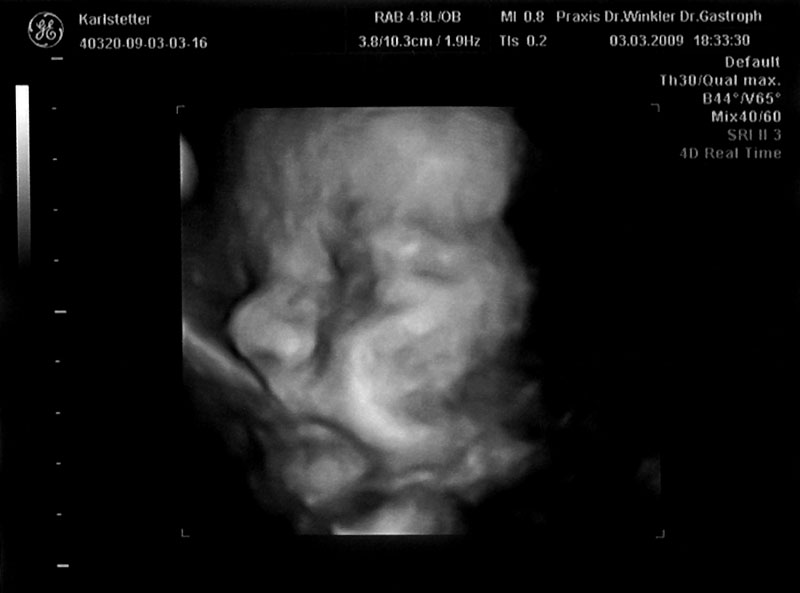

Werfen wir noch kurz einen letzten Blick auf Jonas in seiner „Einzimmerwohnung“.